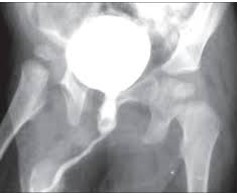

2. Urthrography:

The image of the urethra is done with contrast agent and is one of the most important parts for examining urethral stenosis, which is very important by an experienced technician so that the patient is not harassed and the quality of graphy is acceptable and consists of 2 parts:

- Retrograde urthrography:

A small catheter is placed at the urethra and the contrast agent is injected from it, and the image is taken simultaneously to see the length of the urethral lenght in the graph.

- Voiding cyctourethrography:

The bladder is filled with contrast material and the patient is asked to urinate and the image is taken at the same moment to see the length of the posterior and anterior urethra.